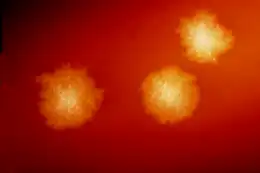

C. difficile toxins have a cytopathic effect in cell culture, and neutralization of any effect observed with specific antisera is the practical gold standard for studies investigating new CDI diagnostic techniques.[20] Toxigenic culture, in which organisms are cultured on selective media and tested for toxin production, remains the gold standard and is the most sensitive and specific test, although it is slow and labor-intensive.[48]